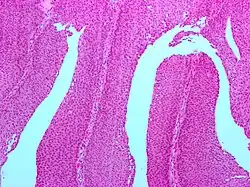

Micrograph of a PUNLMP. Intermediate magnification. H&E stain.

Micrograph of a PUNLMP showing characteristic features (see text). H&E stain.

PUNLMPs are exophytic lesions that appear friable to the naked eye and when imaged during cystoscopy. They are definitively diagnosed after removal by microscopic examination by pathologists.

Histologically, they have a papillary architecture with slender fibro vascular cores and rare basal mitoses. The papillae rarely fuse and uncommonly branch. Cytologically, they have uniform nuclear enlargement.